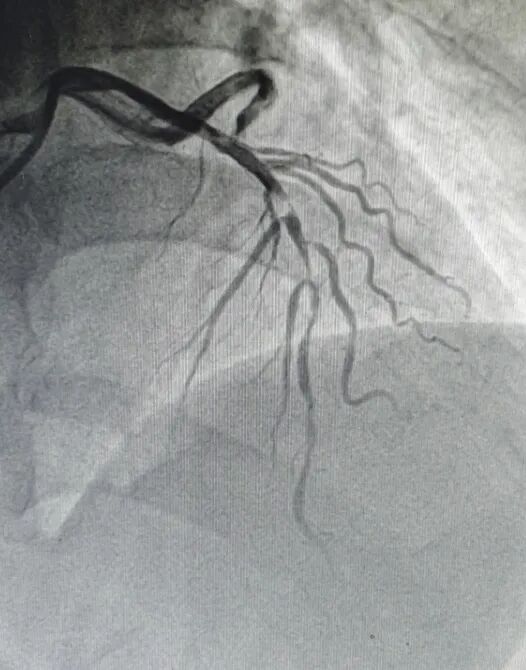

图 | 血管云雾状改变

虽然是午间休息时分,但我院心病二科专家团队奉行全天候24小时待命,在汤华主任的带领下,多科室迅速联动为患者开通绿色通道,第一时间为患者行急诊冠状动脉造影检查,发现血管内大块血栓,即刻进行血管内溶栓治疗,患者转危为安。